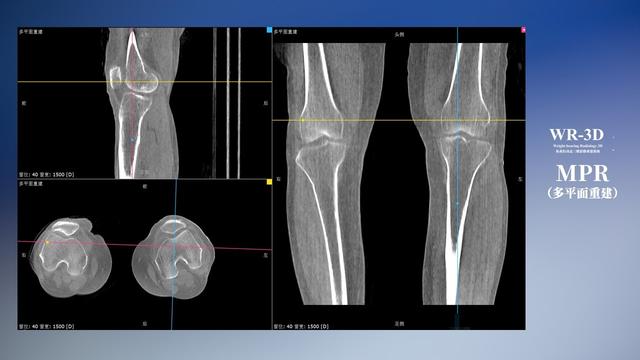

与此同时,数字化X线摄影技术相较于CTMRI来说,能快速获取真实、直观、满足临床需要的影像。DR的图像具有图像层次丰富、空间分辨力高、影像边缘锐利清晰、密度分辨力高级细微结构表现出色等特点,针对膝关节解剖结构数字化X线摄影技术应用价值很高,尤其是是对骨小梁与骨皮质的显示非常清楚。在负重位状态下,数字化X线三维摄影扫描与重建,能够更好的呈现受检者关节受力改变的状态。广东会科技创新的WR-3D动态三维数字化X线摄影技术,通过数字化X线摄影完成三维扫描并重建三维影像信息,包括MPR多平面重建、MIP重建以及VR绘制。扫描时间短,剂量相较于CT设备大幅缩减,同时成本更低,在临床诊断以及医疗方案制定中具有极大的价值意义。相较于普通平片下的负重位扫描,负重位动态三维扫描摄影技术能够避免二维状态下的组织结构重叠、密度分辨率不足、组织解剖结构难以分辨等问题,WR-3D支持多角度的动态三维摄影观察,能全面的呈现被检查部位在多个角度下三维影像信息,极大的减少了二维负重位检查的漏诊率。

广东会科技WR-3D负重位动态三维摄影技术